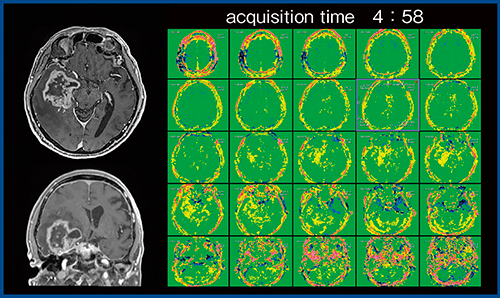

図2の症例について2Dと3Dを比較すると,画像に違いは見られないが,3D収集では撮像に9分ほどかかり,撮像時間が長いことが問題であった。そこで,時間短縮を目的にFFEEPI3Dが開発され,2019年7月より当院にて臨床研究が行われている(図3)。FFEEPI3Dで撮像した症例を示す(図4)。右側頭葉の膠芽腫の症例で,全脳を5mmスライス厚で撮像し,30枚ほどの画像が取得できる。撮像時間は4分58秒と,FFE3Dの約半分に短縮され,十分に使用可能な時間となっている。

図4 FFEEPI3Dによる全脳の画像(図3と同一症例)